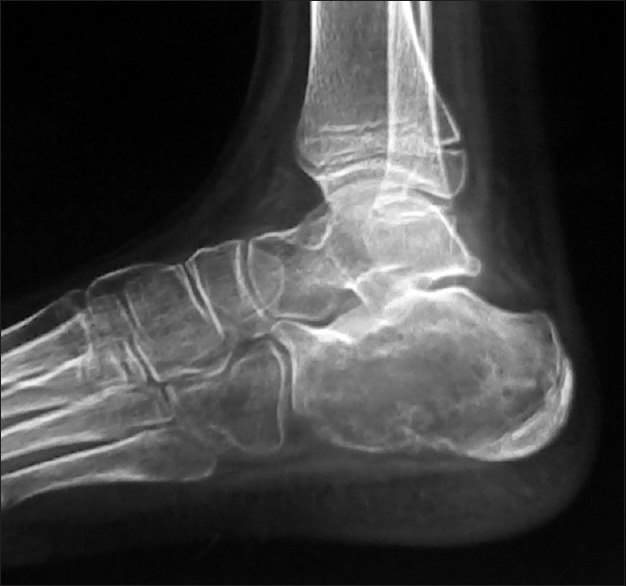

Radiograph of the left heel showed an expansile lytic lesion in the calcaneum with cortical break and no periosteal reaction [Figure 1]. Magnetic resonance imaging (MRI) of the ankle revealed well-defined expansile cystic lesion in the calcaneum. The lesion appears predominantly isointense on T1-weighted imaging and heterogeneously hyperintense in T2-weighted imaging with septations and fluid layering [Figure 2]. There is a breach in the medial aspect with the extension of the lesion into the adjacent soft tissue with enhancement on postcontrast study. The radiologic impression was of aneurysmal bone cyst.

| Figure 1:Radiograph showing well-defined expansile lytic lesion in the calcaneum